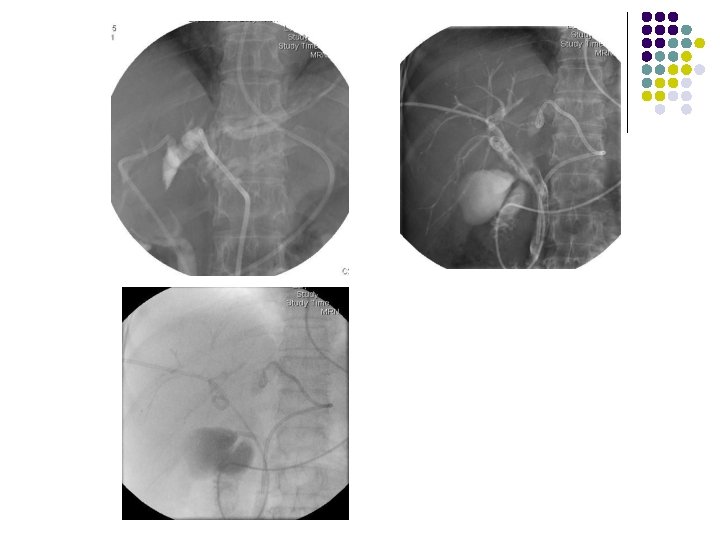

l 79歲 女性 PTGBD